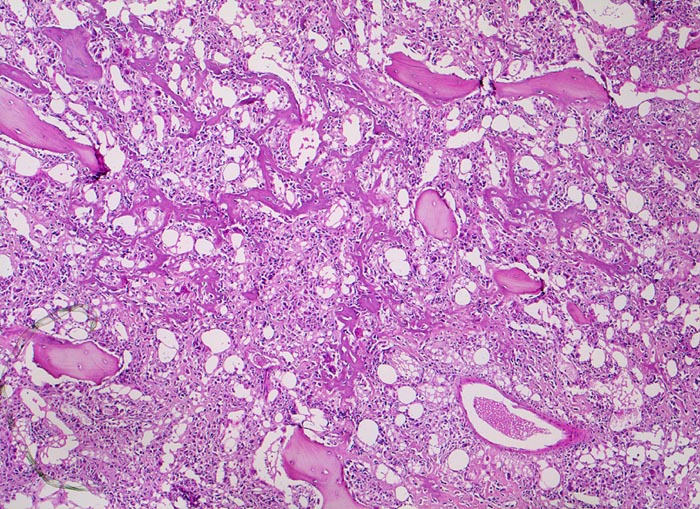

Morphologische Merkmale:

• Tibiametaphyse mit angrenzendem Weichteilgewebe.

• Das Sarkom infiltriert diffus den spongiösen Knochen der Diaphyse und hat präexistente Knochenbälkchen verdrängt.

• Der Tumor hat die Korticalis destruiert und infiltriert die angrenzende Skelettmuskulatur.

• Der Tumor besteht aus neugebildetem bereits verkalktem Knochen oder einem Netzwerk von primitiven Osteoidtrabekeln. Entlang oder innerhalb der Osteoidtrabekel lokalisierte polymorphe Tumorzellen mit ausgeprägten Kernatypien und zahlreichen Mitosen. Leicht verwaschene Kernstrukturen als Folge der Gewebsentkalkung.